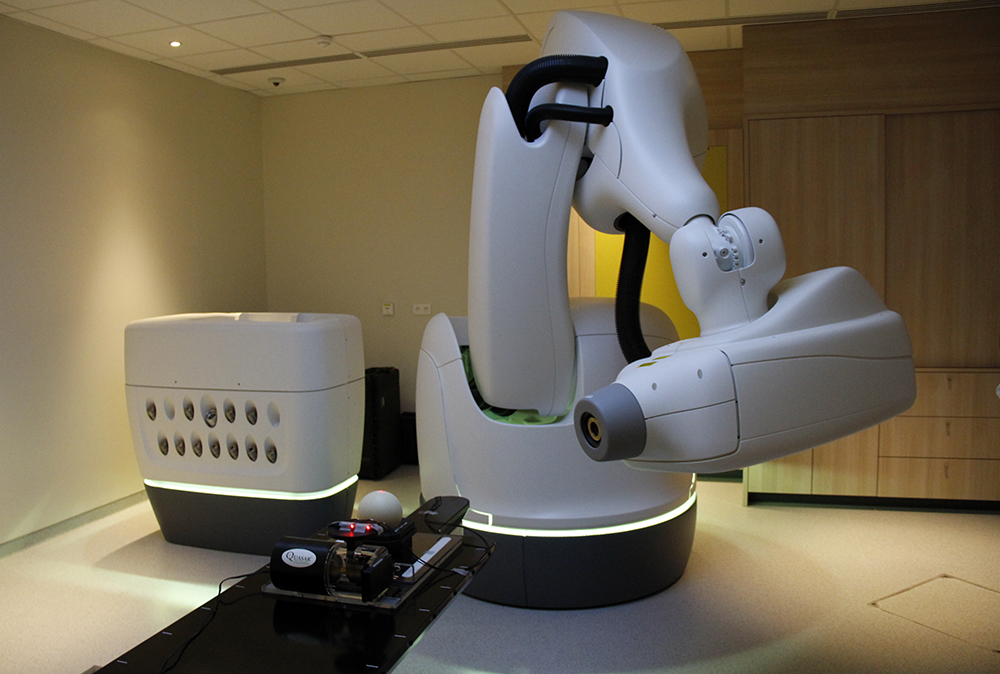

Une salle La Vannetaise inaugurée…

La Vannetaise est fière d’avoir…

La Vannetaise à l’inauguration du…

Programme de recherche centre Gauducheau